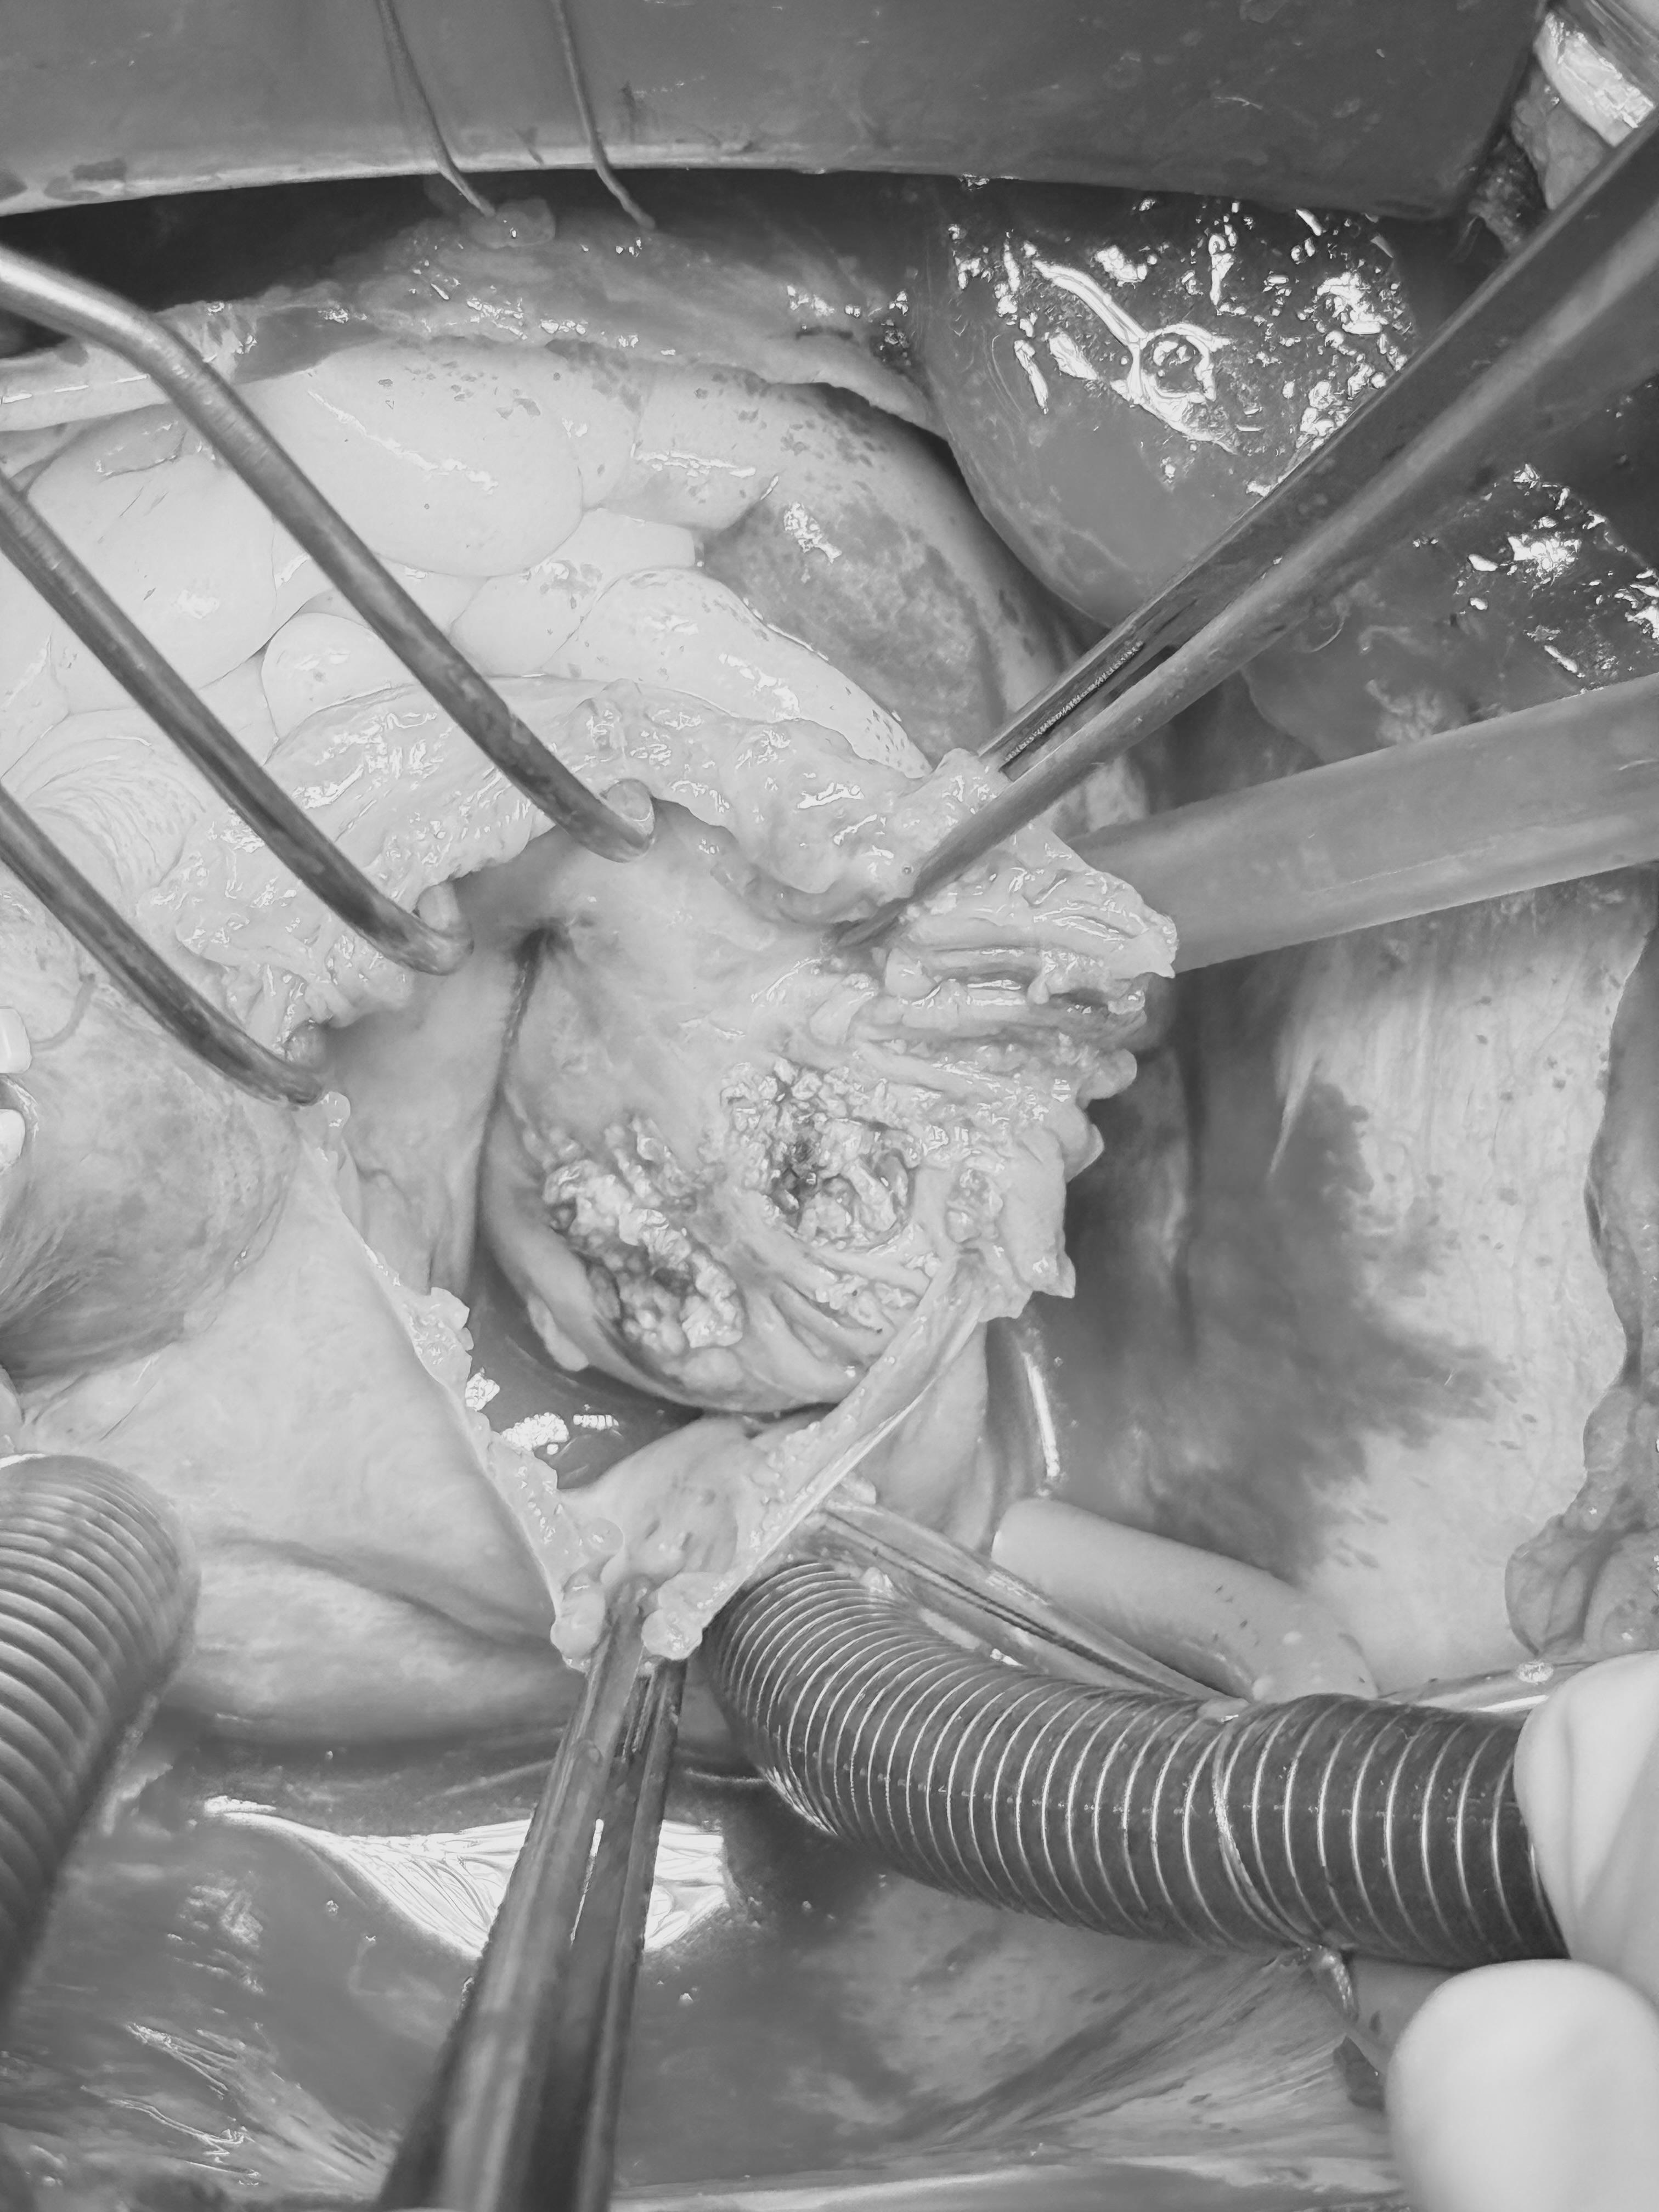

Кардиохирурги БСМП провели тонкую, ювелирную работу. Врачи аккуратно удалили новообразование из сердца пациентки, а затем использовали специальный криозонд. Это инструмент для заморозки живых тканей. На пораженную область, в местах иссечения опухоли, хирурги воздействовали низкими температурами (до -70 °C). Это было сделано для того, чтобы не допустить дальнейшего разрастания опухоли. После удаления материал отправили на гистологию. Опухоль оказалась доброкачественной.

Гарма Майоров, сердечно-сосудистый хирург БСМП: «Миксома сердца – это достаточно редко встречающееся доброкачественное образование. В нашем случае опухоль достигла больших размеров: 6*8 см. Она крепилась широким основанием к передней стенке сердца, была мягкой консистенции, по виду напоминала грозди винограда. Поэтому при удалении она начала распадаться на части. Главной нашей задачей было не только очистить сердце от опухоли, но и не допустить дальнейшего распространения миксомы. Для этого мы заморозили стенку предсердия специальным криозондом. Такой метод называется криоабляция.

Кроме того, из-за больших размеров опухоли, трехстворчатый клапан сердца деформировался, мы вернули ему прежнюю форму, сделав пластику. Во время операции, чтобы снять нагрузку с сердца, мы его остановили. Все функции выполнял аппарат искусственного кровообращения».